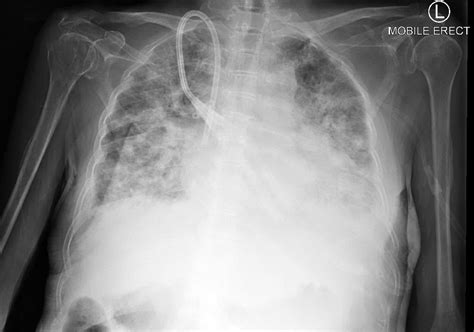

Differentiating Cardiogenic from Non-Cardiogenic Edema

While the Pulmonary Edema Cxr is excellent at confirming the presence of fluid, determining the etiology is equally important. Cardiogenic pulmonary edema is typically associated with a widened cardiothoracic ratio (cardiomegaly) and vascular redistribution. In contrast, non-cardiogenic pulmonary edema, often seen in Acute Respiratory Distress Syndrome (ARDS), usually presents with a normal heart size, patchy or peripheral infiltrates, and an absence of pleural effusions.

Clinicians utilize the X-ray in conjunction with lab tests like Brain Natriuretic Peptide (BNP) to make a definitive diagnosis. If the heart shadow is enlarged, it strongly suggests a cardiac origin, whereas a normal-sized heart with widespread bilateral infiltrates warrants an investigation into sepsis, transfusion-related lung injury, or other non-cardiac triggers.

Technical Considerations in Imaging

To obtain an accurate Pulmonary Edema Cxr, technical factors must be optimized. Portable bedside chest X-rays, common in critical care settings, are often performed in an anteroposterior (AP) projection. This projection can artificially magnify the heart size, making it difficult to differentiate mild cardiomegaly from normal variants. Therefore, standardized positioning is vital for consistent interpretation.